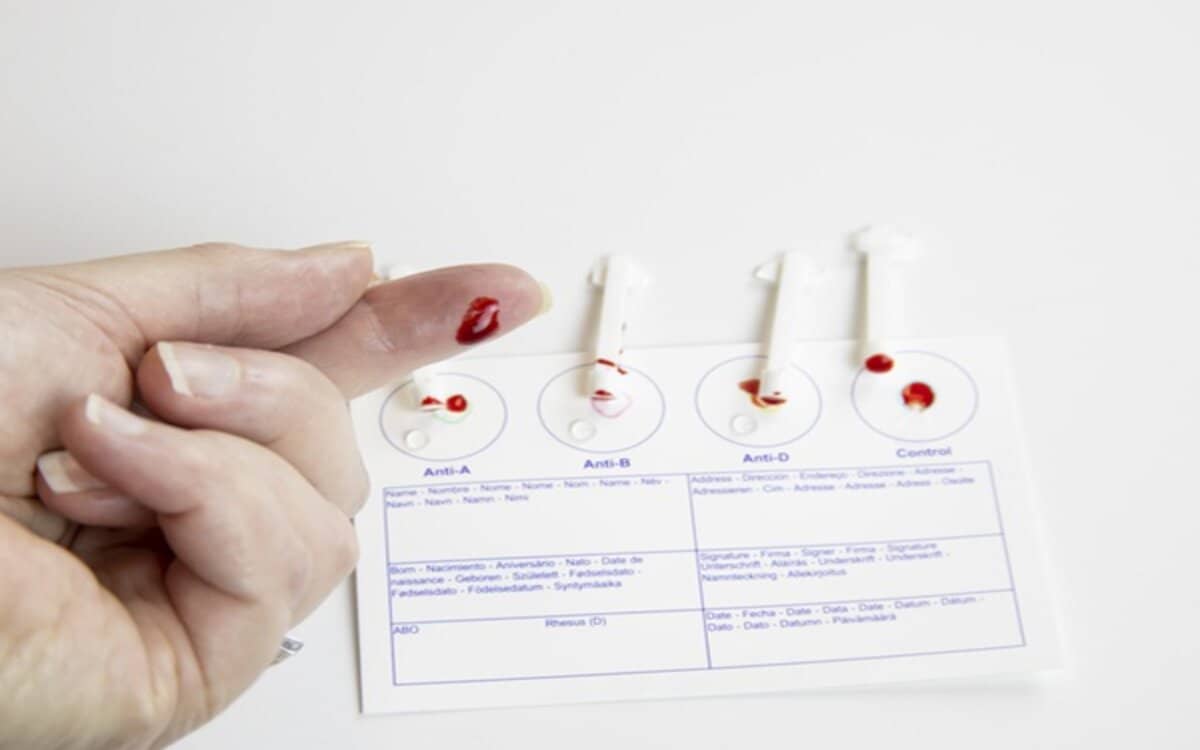

تحليل فصيلة الدم هو اختبار بسيط يهدف إلى تحديد فصيلة الدم للشخص، ومعرفة إذا ما كان لدى الشخص مادة تسمى بالعامل الرايزيسي أو RH أم لا، وهي عبارة عن بروتينات أو مستضادات تظهر على سطح خلايا الدم الحمراء، والتي تعد شديدة الأهمية بالنسبة للنساء الحوامل لمعرفة مدى تطابق فصيلة الدم بين الأم والجنين.

ويعتمد نوع فصيلة الدم على الجينات التي يرثها الفرد من الوالدين، إلا أن جميع البشر يتكون الدم لديهم من نفس الأجزاء الأساسية مثل خلايا الدم الحمراء والبيضاء والصفائح الدموية والبلازما، ولكن ليس الجميع لديهم توافق في فصيلة الدم، فهناك تنوعًا كبيرًا في أنواع الدم.

وتُقسم فصيلة الدم إلى 8 مجموعات رئيسية هي كالتالي :

- فصيلة الدم A+

- فصيلة الدم A-

- فصيلة الدم B+

- فصيلة الدم B-

- فصيلة الدم O+

- فصيلة الدمO-

- فصيلة الدم AB+

- فصيلة الدم AB-

ويمكن إجراء تحليل فصيلة الدم من خلال سحب عينة من دم الشخص باستخدام إبراة من قبل فني المعمل، ويمكنك شراء اختبار الدم عبر الإنترنت لإجراء التحليل في المنزل.

كذلك يمكنك معرفة نوع فصيلة دمك عند التبرع بالدم، وبعد التبرع تُعطى بطاقة متبرع بالدم تتيح لك الوصول إلى فصيلة الدم عند اختبارها، وهو فحص مجاني.